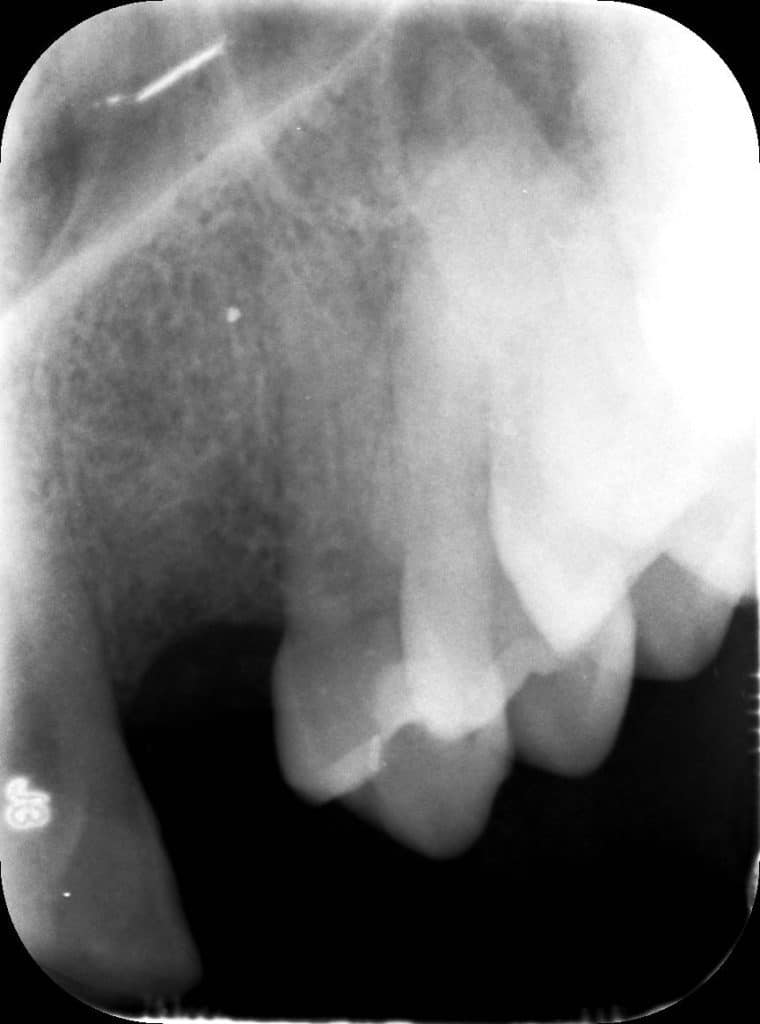

La pz N.G. di anni 52 (ASA 1) viene visitata nel mese di settembre 2017 per la mobilità ed inestetismo dell’elemento protesico 22, (foto iniziali sequenza 1) si evidenzia una frattura parziale della radice, si decide per l’estrazione ( foto sequenza 2) e sostituzione dell’elemento con un restauro implanto-protesico. Purtroppo la scarsa quota ossea apicale all’alveolo post-estrattivo (foto 2 rx) e l’alta valenza estetica dell’elemento ci rende cauti e si programma una socket preservation post estrattiva con l’ausilio delle membrane di prf (foto prf e socket sequenza 3 e 4). Durente i 5 mesi di guarigione la pz porta una protesi parziale mobile (foto 5,2) , a guarigione del sito post estrattivo si evidenzia una buona conservazione dei volumi osseo-gengivali,(foto guarigione sequenza 6) se pur presente una recessione distale all’elemnto 21.Nel mese di febbraio 2018 si procede all’inserimento di un impianto max-stability 3,75x12mm disegnando un lembo anticipato palatino per consentire un aumento dei tessuti vestibolari suturando con tecnica rool flap e trasformando l’elemento parziale mobile in una corona singola a carico immediato sul moncone temporameo applicando i concetti protesici bopt , (foto impianto moncone protesi provvisoria sequenza foto 7-8-9). Durante il periodo di maturazione dei tessuti molli vengono apportate opportune modifiche ai profili del provvisorio al fine di dare maggior spazio al tessuto gengivale, ( fotosequenza 10).Dopo circa 2 mesi dal protesizzazione provvisoria si è proceduto alla realizzazione del manufatto protesico con tecnica chair side sirona con l’ausilio del t-base (foto sequenza 11-12-13), realizzando in una sola seduta una corona in disilicato, ottenendo un risultato più che soddisfacente (Foto 14). Nel controllo a 3 mesi dal carico definitivo si apprezza la perfetta conservazione dei livelli ossei e gengivali. (foto sequenza 15).concludo con un follow up a 18 . Tengo a sottolineare che un caso come questo è stato conducibile con buoni risultati solo grazie alla piena fiducia della pz e alla sua massima motivazione e collaborazione. Ad oggi la pz sorride soddisfatta del risultato. E questo rappresenta la massima ricompensa di chi dedica tutto se stesso alla professione.